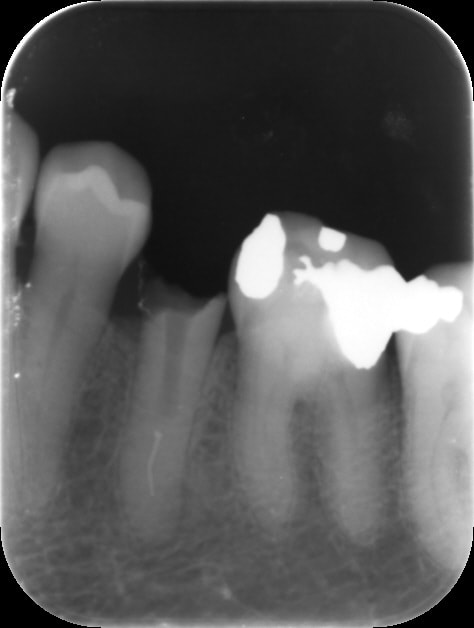

petit exemple où je n'ai pas été foutu d'instrumenter jusqu'à l'apex et où j'ai balancé la purée en profondeur. J'ai mis un petit amalgame pour faire plaisir à Gépé le temps que ça cicatrise.

Pour revenir à la radio de départ : est-ce un puff ou bien un artefact que l'on voit sur la radio de l'obturation ? Et si le foramen était franchement distal, pas à l'apex du tout ? Ce serait cohérent avec la morphologie de la LIPOE bien visible sur la radio pré-op.

C'est un puff , sinon oui c'est sûr et certain la sortie du canal est en latéral. Mais j'ai pas réussi à y accéder avec mes limes.